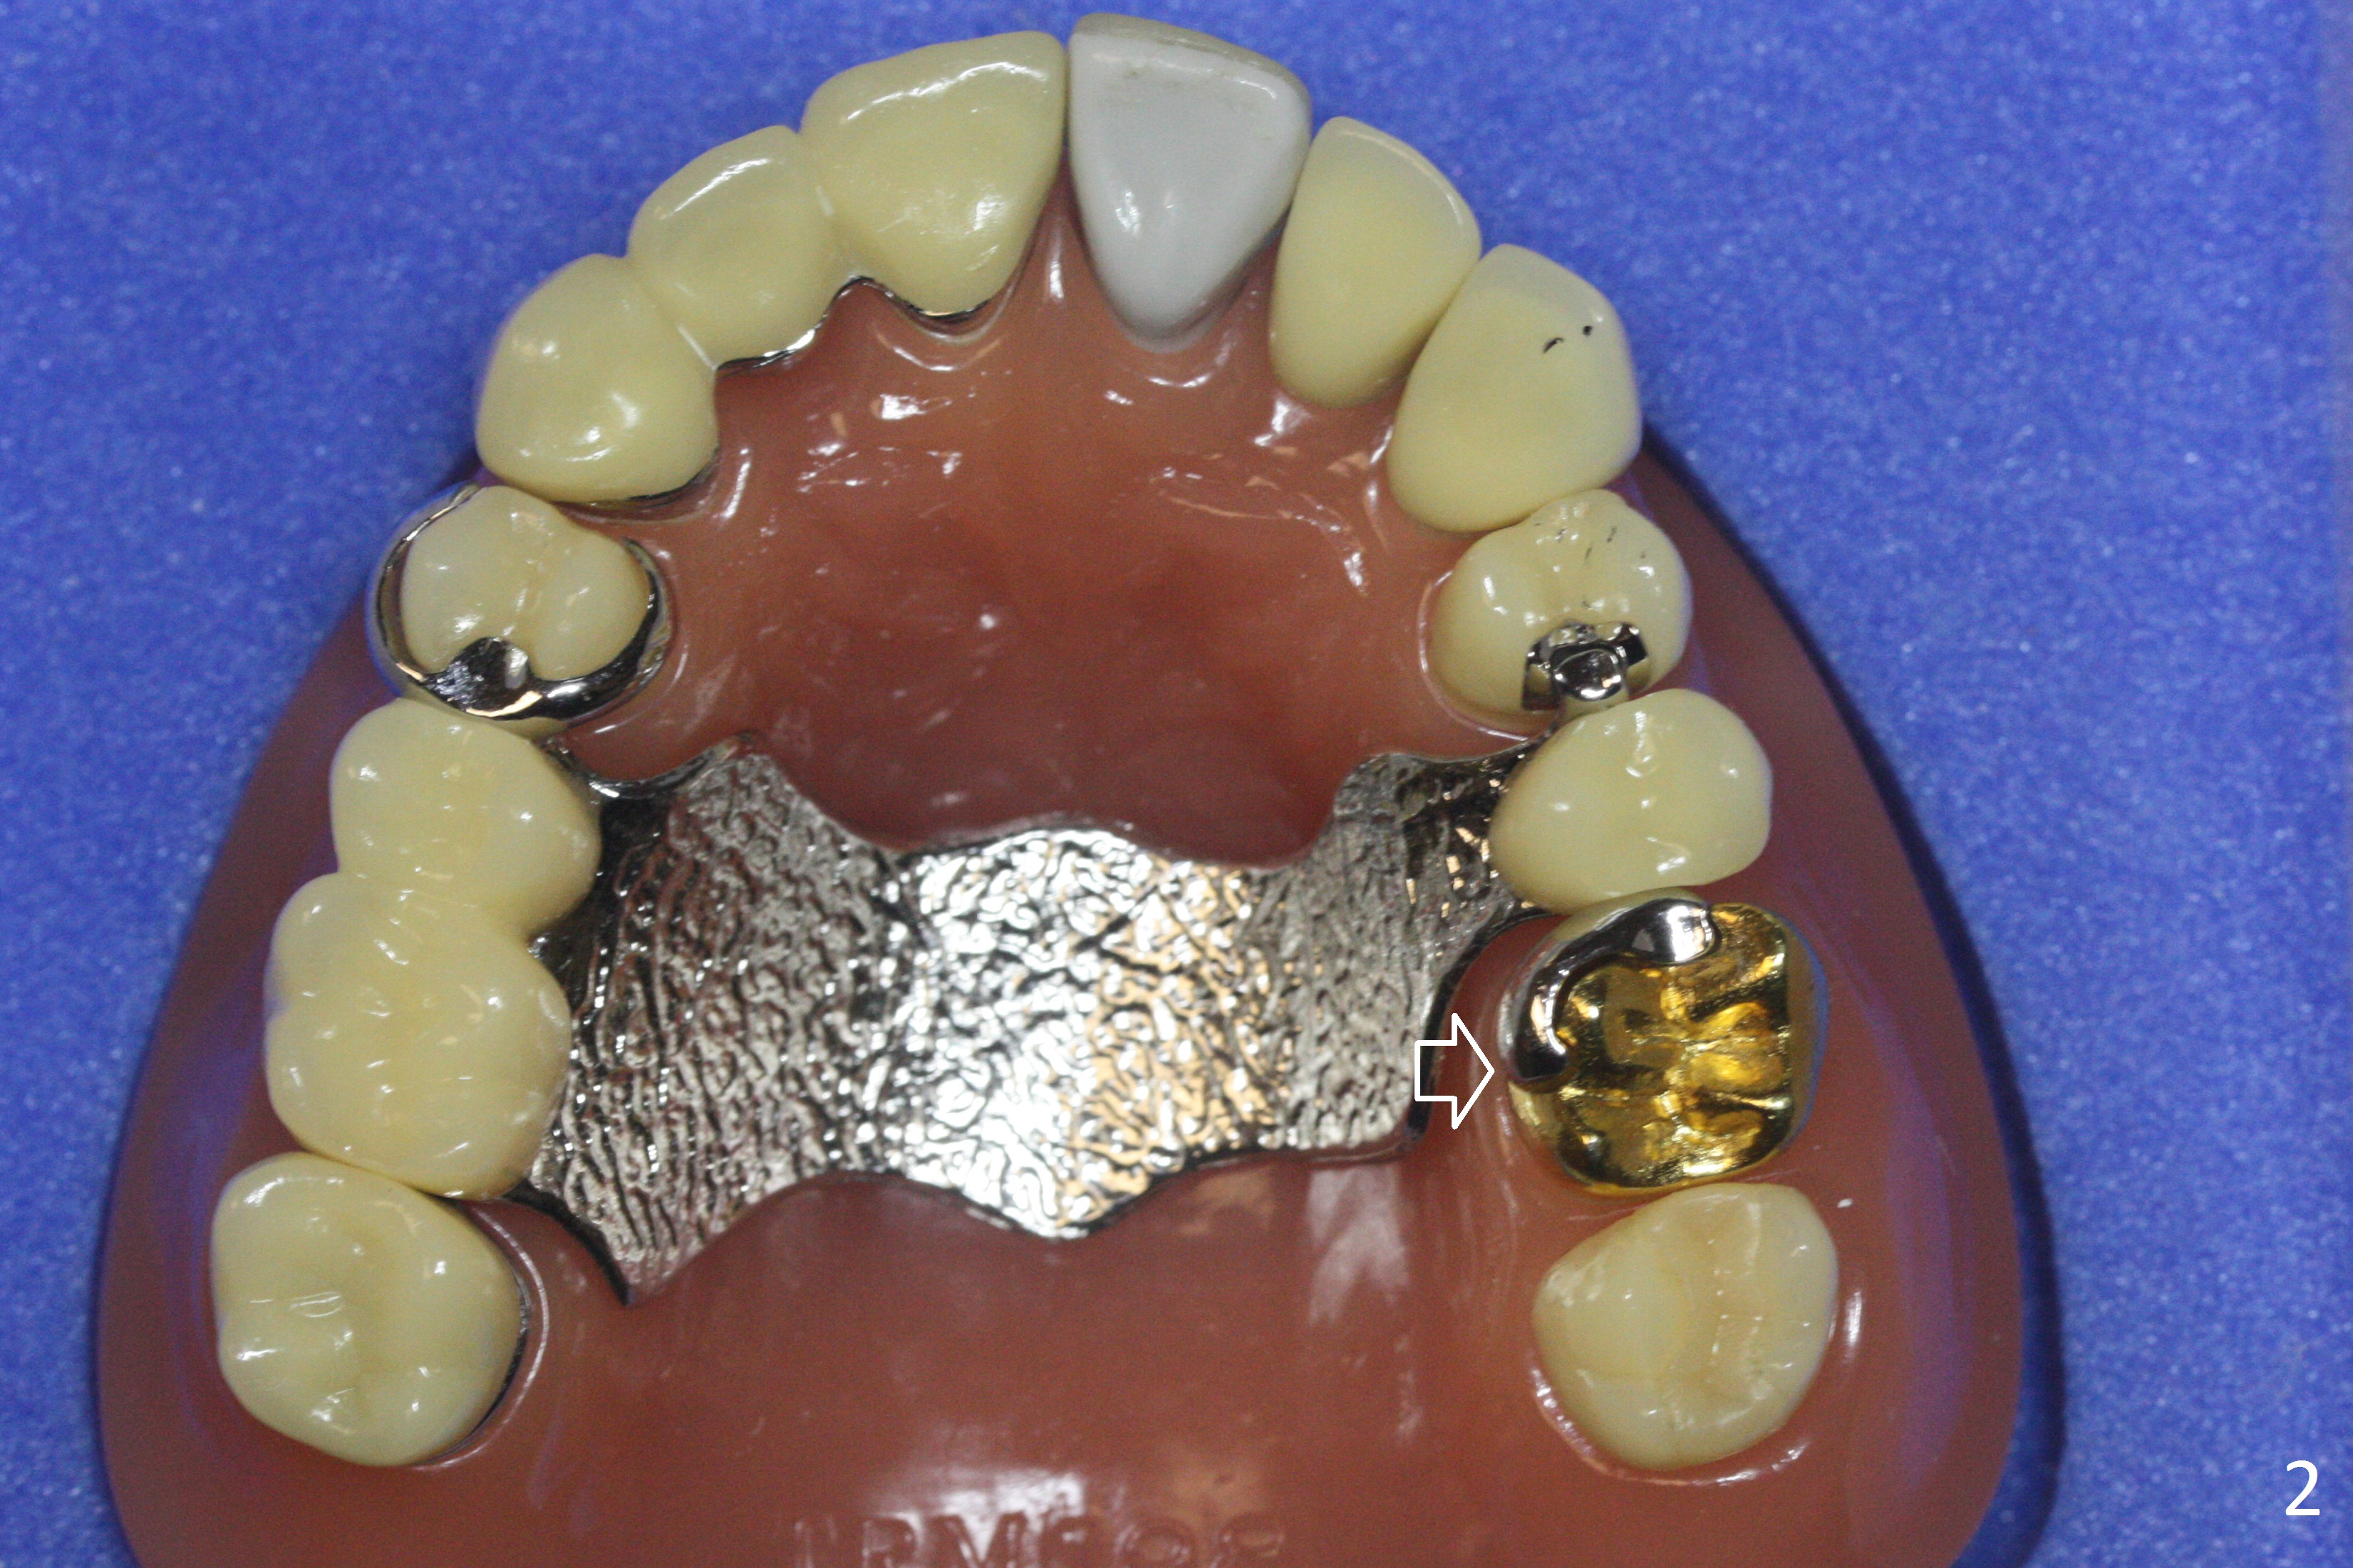

Also simplify design.  For example, in a demonstration model, there is mesiopalatal prep in the crown at #14 (Fig.1 arrow).  The lingual clasp is short, stopping the distal end of the prep (Fig.2 arrow).  There is no buccal clasp.